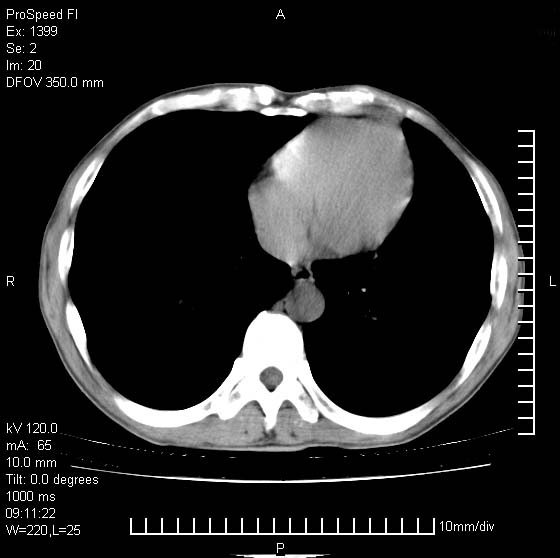

以下是引用卜一在2007-1-19 9:55:00的发言:[br]左肺沿胸膜下巨大肿块影,边缘呈分叶征,纵隔内见肿大淋巴结,右肺内另见一不规则结节影 .考虑:左肺周围性肺癌伴纵隔 右肺内转移.

以下是引用rgsyyf在2007-1-19 11:05:00的发言:[br]左肺上叶见形态不规则巨大软组织肿块影,边缘呈分叶征,纵隔内隆突下见肿大淋巴结,右肺内另见一不规则结节影 .考虑:左肺周围性肺癌伴纵隔即右肺内转移.